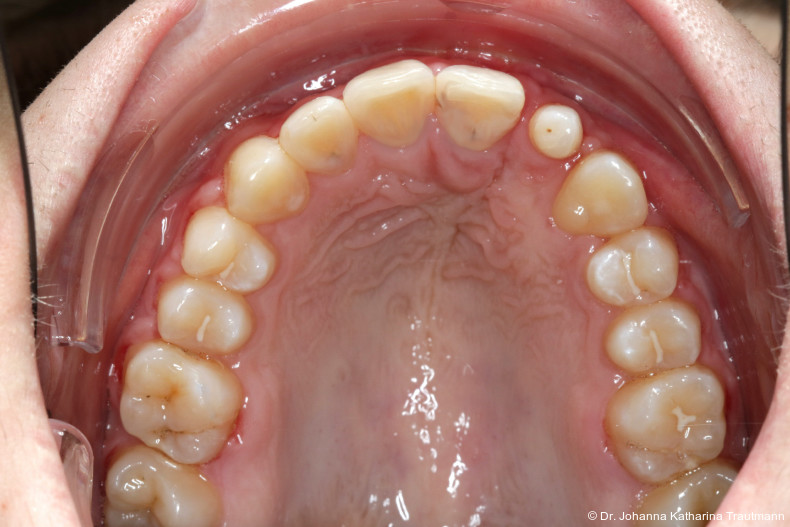

Das Fernröntgenseitenbild zeigte eine skelettale Klasse IIAnomalie mit einem Wits von 5,6 mm, bei einer tiefen Konfiguration (ML NL = 16,5°) mit bialveolär retrudierten Fronten (OK1NA = 5,9°; UK1NB = 10,4°), was sich auch in der Modellanalyse widerspiegelte. Hier zeigte sich zudem ein schmaler Oberkiefer mit multiplen Kippungen und Rotationen in der Front, einem hypoplastischem 22 sowie einer Mesialwanderung des 16. Des Weiteren zeigte sich eine asymmetrische Bisslage mit 1 PB distal rechts und ½ PB distal links bei einem Overjet von 2,5 mm sowie einem Overbite von 5 mm. Während im Unterkiefer bereits die zweite Zahnwechsel phase begonnen hatte, zeigte sich im Oberkiefer noch kein Wechsel in den Stützzonen. Gerade bei Patienten mit Spaltbildungen ist eine engmaschige Überwachung des Durchbruchs der oberen Eckzähne essenziell. Während bei der Allgemeinbevölkerung die Prävalenz von verlagerten Eckzähnen bei ca. 2,8 Prozent liegt2, ist diese bei Patienten mit Lippen-Kiefer-Gaumen-Spalten um den Faktor 10 erhöht.3, 4 Als klassische Risikofaktoren gelten zudem Platzmangel, transversale Enge aber auch Fehlstellungen, Nichtanlagen oder Hypoplasien der zweiten Schneidezähne. Diese übernehmen normalerweise die Funktion der Leitschiene für den S-förmigen Durchbruch der Eckzähne. Im vorliegenden Patientenfall kommen also mehrere Risikofaktoren für eine Verlagerung zusammen, was die rechtzeitige Diagnostik zur Abklärung einer Durchbruchsproblematik rechtfertigt. Da im Spaltbereich auch zusätzlich ein ausgeprägtes Knochendefizit vorliegen könnte, sollte auch immer die Option einer sekundären Osteoplastik abgewogen werden, deren Indikation und Timing optimal zum Durchbruch der Canini angepasst werden sollte.5

Nach transversaler Nachentwicklung der Maxilla mittels GNE nach Veltri wurde der Zahn 23 geschlossen freigelegt und an einem individualisier ten TPA nach distal angebunden. Zur Aufrichtung der Front und Mesialisierung des hypoplastischen Zahnes 22 kam zusätzlich eine 2x3Mechanik zum Einsatz. Eine rein translatorische Bewegung eines Zahnes ist auch mit einer festsitzenden Apparatur schwer zu erreichen, da der Kraftansatzpunkt nicht identisch mit dem Widerstandszentrum des Zahnes ist.7 Diese Problematik kann einerseits durch das Einbringen eines Versetzungsmomentes adressiert werden, andererseits durch eine Verlagerung des Kraftansatzpunktes. Angelehnt an den von Hong et al. beschriebenen Power Arm 8 wurde hierfür palatinal an Zahn 22 ein cranial gerichteter Hook angebracht (Abb. 3). Da Zahn 22 aufgrund seiner Hypoplasie eine verkürzte Wurzel aufwies, konnte so die Distanz zwischen Widerstandszentrum und Kraftangriffspunkt effizient reduziert werden. Eine weitere biomechanische Schwierigkeit stellte das geringe Alveolarknochenangebot im Spalt bereich mesial von 22 dar. In Bereichen mit Knochendefizit verschiebt sich das Widerstandszentrum nach apikal und wie in diesem Fall zusätzlich nach distal.9, 10 Um dem erhöhten Risiko für Kipp bewegungen entgegenzuwirken, muss hier besonders auf die Steuerung des M/F-Quotienten geachtet werden. Der vestibulär durchgebrochene Zahn 13 benötigte keine Freilegung. Um seine korrekte Einstellung zu ermöglichen, wurde die Mesialwanderung des Zahnes 16 mithilfe des TPAs korrigiert sowie eine Mittellinienkorrektur nach links mittels 2x3 Mechanik durchgeführt.